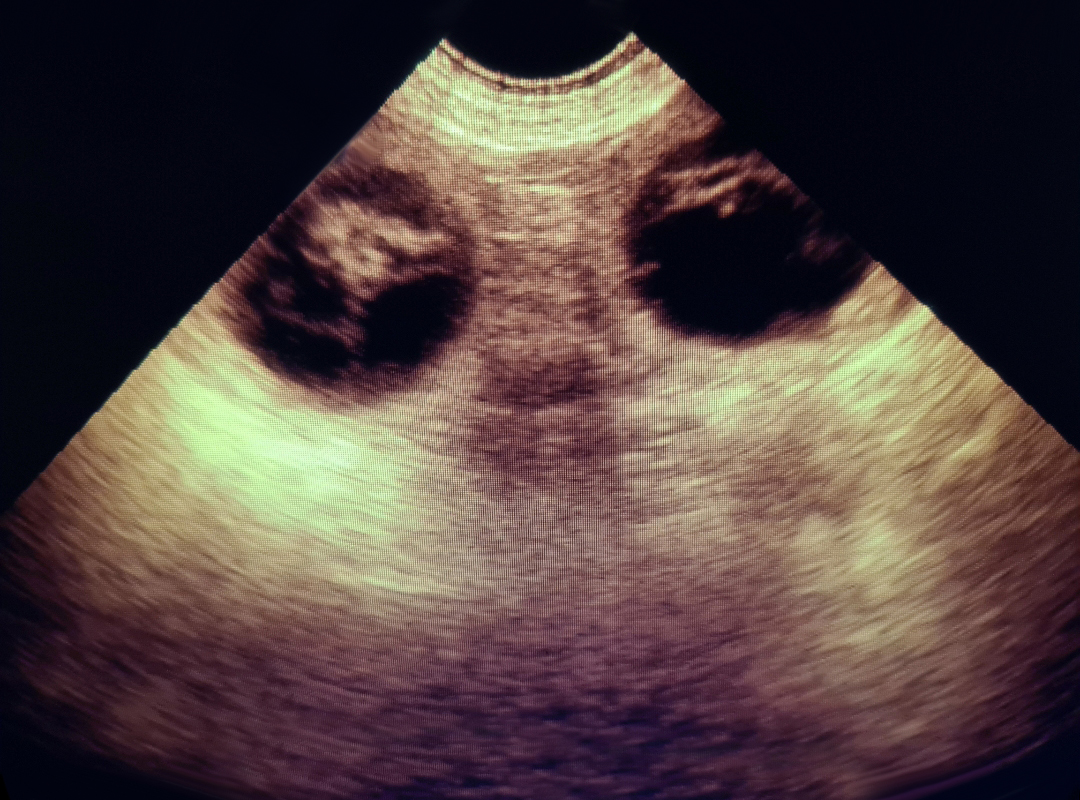

If you believe your pet may be pregnant, we offer gentle and completely painless ultrasound scans to help confirm pregnancy in dogs and cats. These scans can typically be performed from around 28 days after mating.

During the scan, your pet remains calm and comfortable with you gently holding them. A small amount of gel is applied to their abdomen, and a handheld probe is moved carefully over the area to view any developing puppies or kittens.

Using a reliable Scan Pad Ultrasound scanner, Julie can confirm pregnancies and provide you with email copies of any images showing puppies.